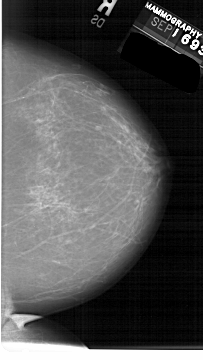

A_1549_1.LEFT_CC

LEFT_CC LINES 6586 PIXELS_PER_LINE 3631 BITS_PER_PIXEL 12 RESOLUTION 43.5 OVERLAY